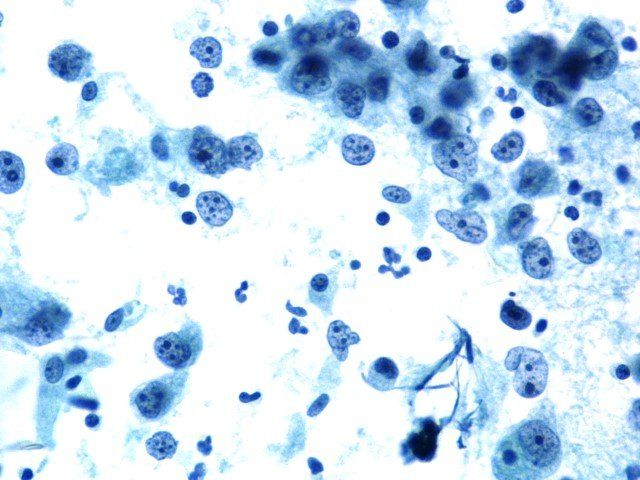

Papanicolaou - Diagnostisch cytologieschema

Dit is een voorbeeld van een lichaamsholtevloeistof gekleurd door Papanicolaou. De dikte van de preparatie is ongelijk. De nucleaire kleuring is te intens, maskeert de cytoplasmatische kleuring en er is onduidelijk chromatinedetail. Deze dia scoort een 6/10.